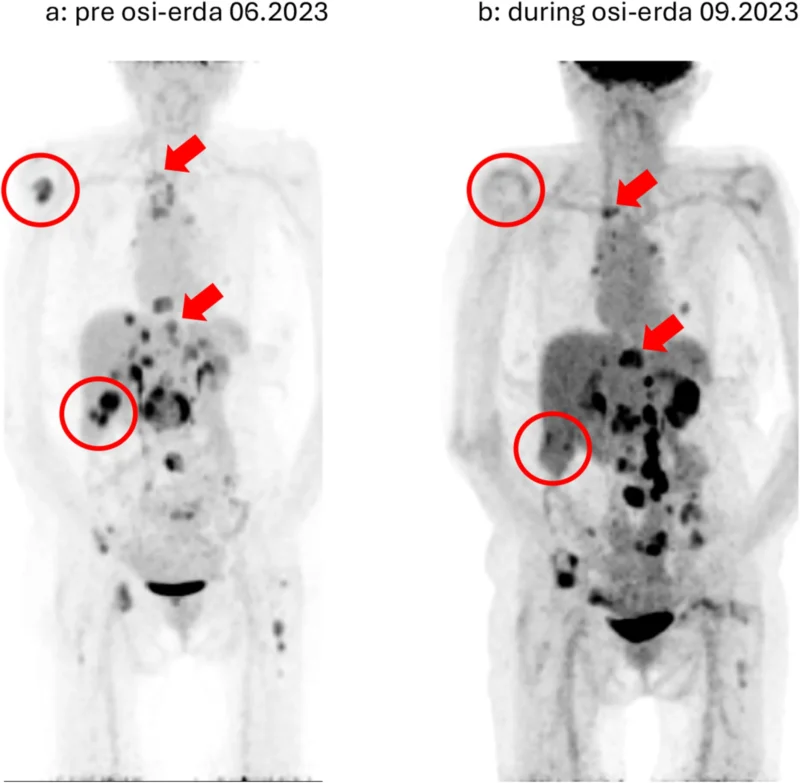

This time, analysis revealed the emergence of an FGFR fusion, representing a distinct bypass pathway driving tumor growth. FGFR alterations are less common compared to MET amplification but are increasingly recognized as contributors to resistance in EGFR-mutant NSCLC (Kalofonou et al., 2026).

The identification of this new molecular driver prompted a change in therapeutic strategy. The patient was switched to a combination of osimertinib and erdafitinib, an FGFR inhibitor. This sequential targeting of evolving resistance mechanisms led to another favorable clinical response.

This phase of treatment highlights a critical principle in modern oncology: resistance is not a single event but a continuous process of clonal selection and evolution. Each new resistance mechanism may represent a new therapeutic opportunity if appropriately identified.